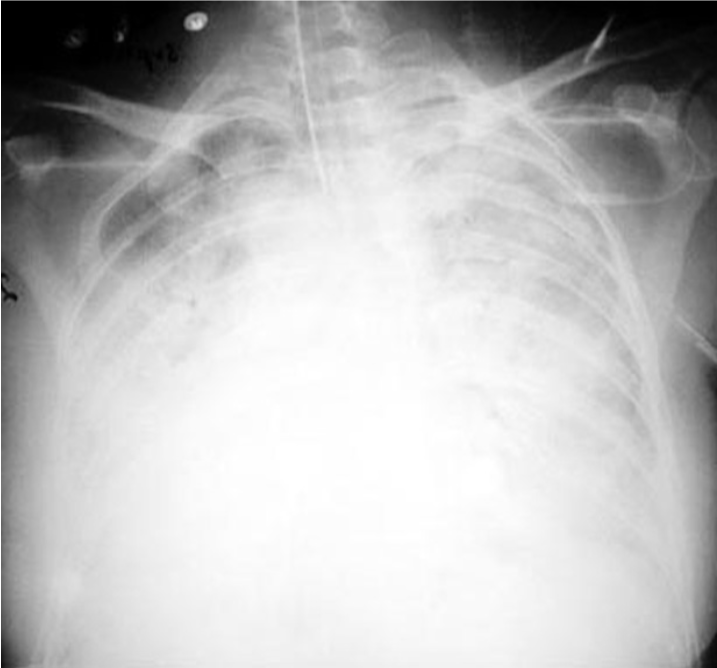

What type of atelectasis is this?

Adhesive